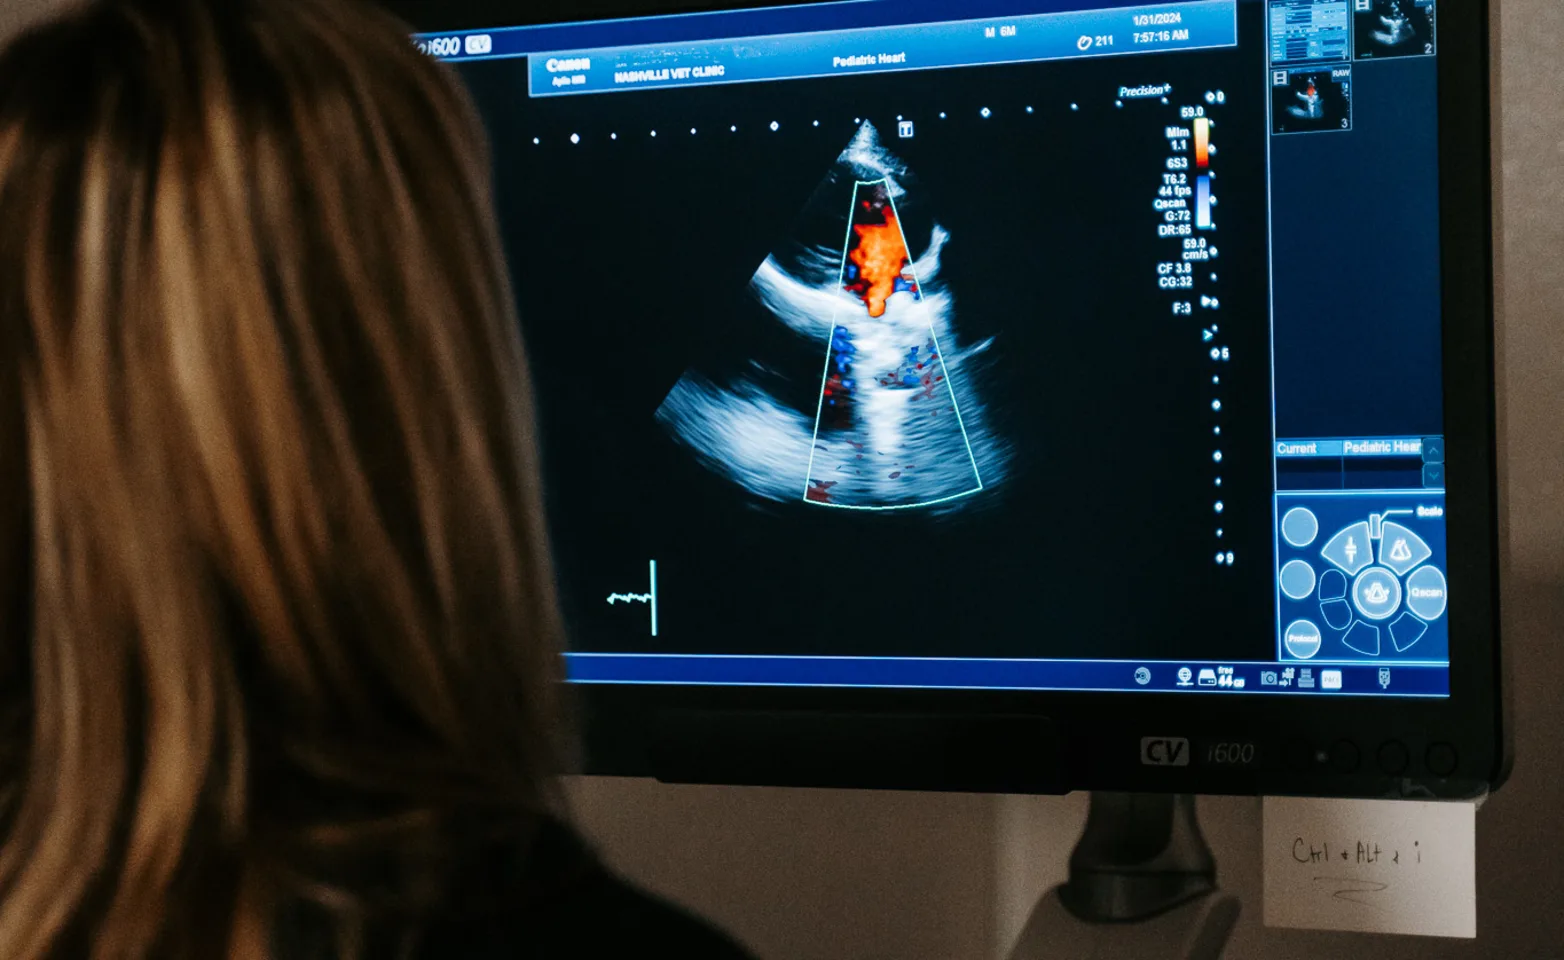

Echocardiogram

Veterinary interventional cardiology is a specialized field focused on diagnosing and treating heart conditions in animals using minimally invasive procedures. At our animal hospital, we offer advanced interventional cardiology services to address a wide range of cardiovascular issues, such as congenital heart defects, arrhythmias, and valve diseases. Our board-certified cardiologists, utilize state-of-the-art equipment and techniques, including catheter-based interventions, to improve the heart health of your pet with less pain and faster recovery times compared to traditional surgery. Whether managing chronic conditions or performing life-saving emergency procedures, our team is dedicated to providing the highest level of care for your pet's heart.